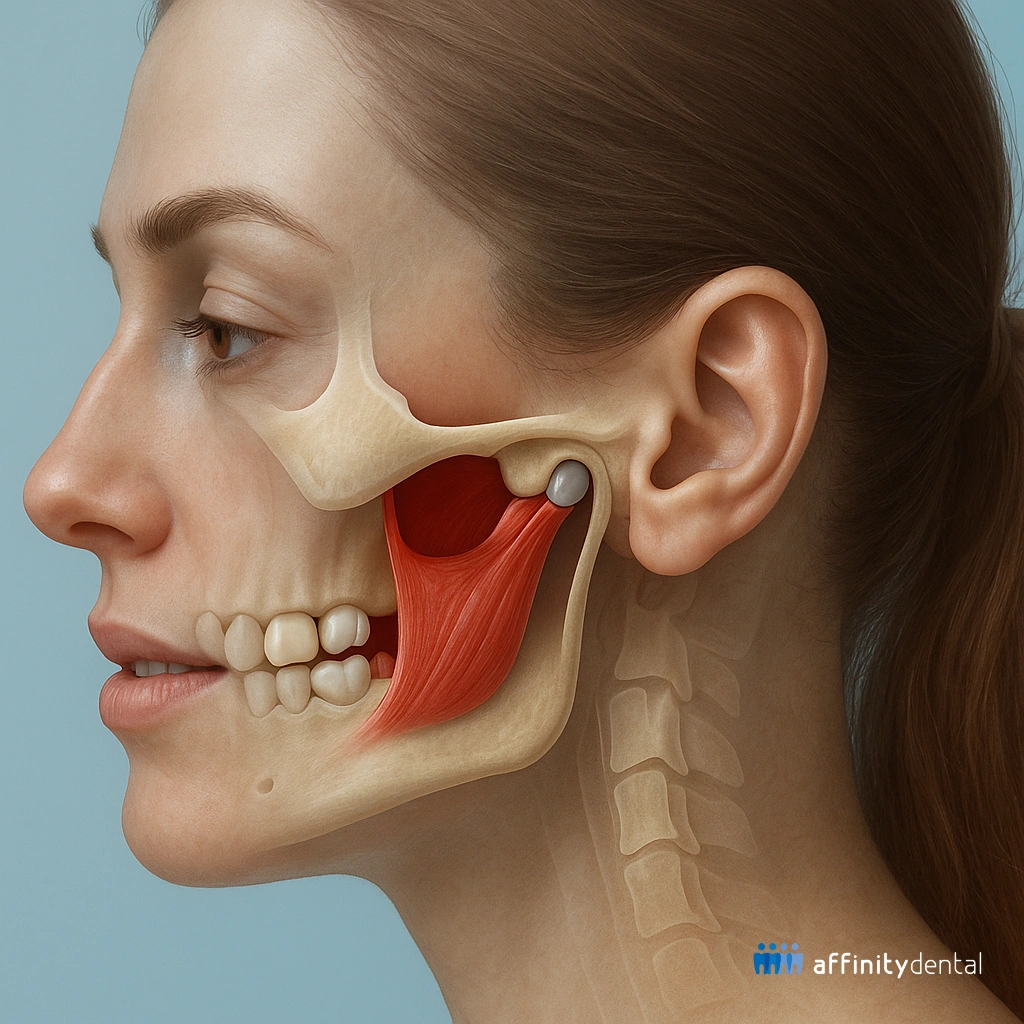

When patients experience jaw pain, clicking sounds, or difficulty opening and closing their mouths, the issue often lies deeper than the teeth—it may involve the temporomandibular joint (TMJ). At Affinity Dental Clinics, we use a highly specialized diagnostic tool known as the Transcranial X-Ray to evaluate the TMJ and its surrounding structures.

A Transcranial X-Ray is a type of lateral skull X-ray that focuses on the temporomandibular joint—the hinge that connects your jawbone to your skull, located just in front of your ears. This imaging allows your dentist or oral surgeon to see both the right and left TMJs clearly, in a closed-mouth and open-mouth position.

TMJ Pain Is More Common Than You Think

If you regularly experience:

• Difficulty chewing

• Tension headaches

• Limited jaw movement

• A clicking or popping sound when opening your mouth

…you might be dealing with TMJ dysfunction, and a Transcranial X-Ray can help us figure out what’s going on.

At Affinity Dental Clinics, we take these symptoms seriously. TMJ issues can affect your overall quality of life, including how you eat, speak, and sleep. A proper diagnosis using a Transcranial X-Ray helps us avoid guesswork and plan a treatment that truly fits your needs.